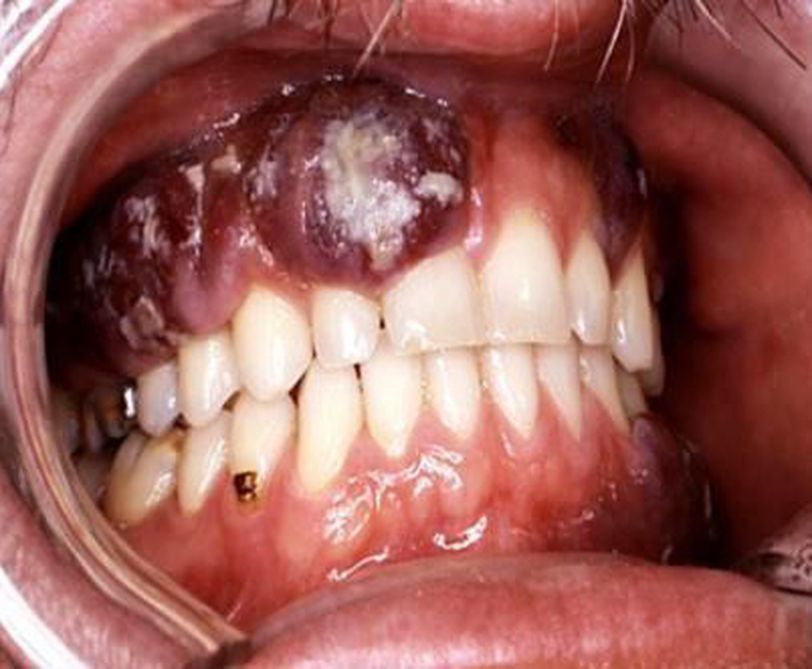

Kaposi sarcoma abbreviated as KS is a type of tumor that is developed due to an HHV8 (human herpesvirus 8) infection; with another name as Kaposi's sarcoma-associated herpes virus or KS agent.This condition has been linked as one of the defining illnesses of AIDS (acquired immunodeficiency syndrome). It is a systemic viral infection affecting the integumentary system, the mouth and the lymph nodes of an affected person, and has the tendency to affect other organs of the body such as the gastrointestinal (GI) system and the respiratory system.